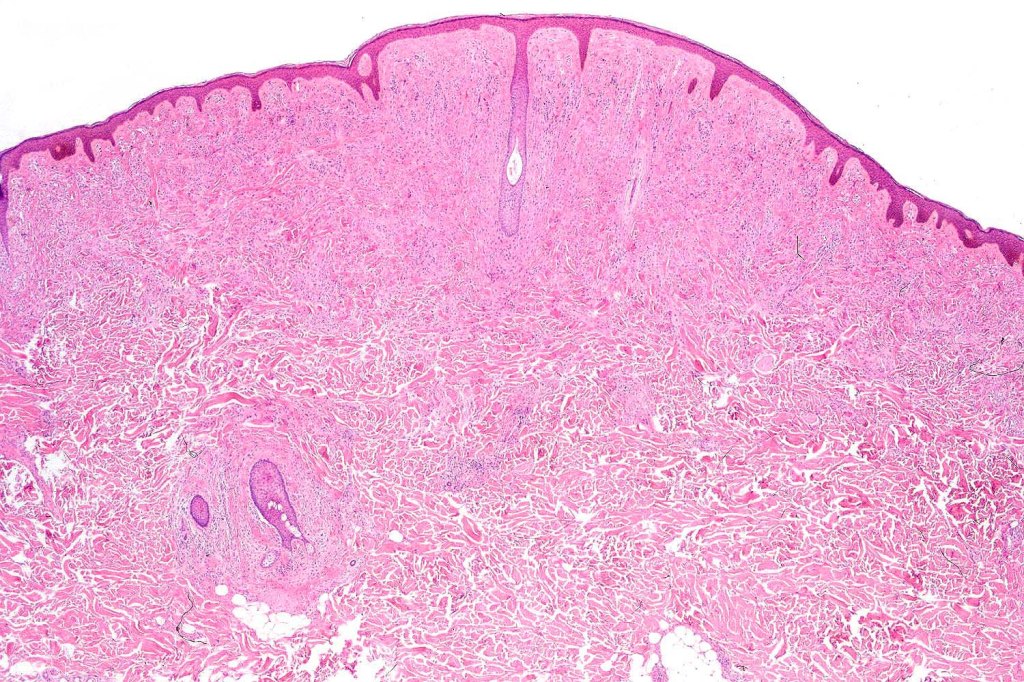

•Silhouette is either wedge-shaped or plaque-like

•Residual Spitzoid junctional nests sometimes evident

•In some cases, nested collections of spindle or epithelioid cells are present in the superficial dermis